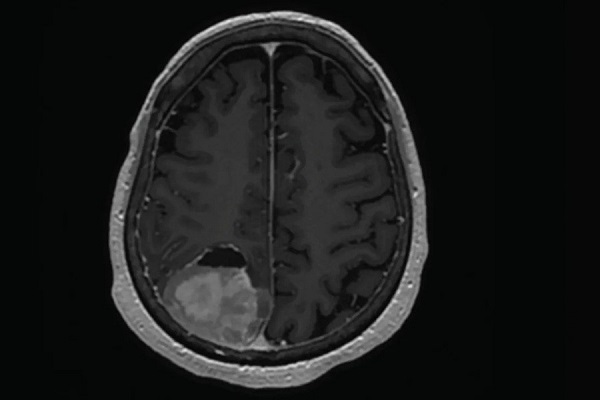

اولین و مهمترین ابزار برای تشخیص تومور، روشهای تصویربرداری پیشرفته هستند. امآرآی (MRI) و سیتی اسکن (CT Scan) به پزشک اجازه میدهند تا تصویری دقیق از ساختار داخلی بدن به دست آورد. بهویژه در موارد مشکوک به تومور مغزی، MRI با جزئیات بالا میتواند اطلاعات کاملی از محل، اندازه و تاثیر توده بر بافتهای اطراف ارائه دهد و به جراح در برنامهریزی کمک کند.